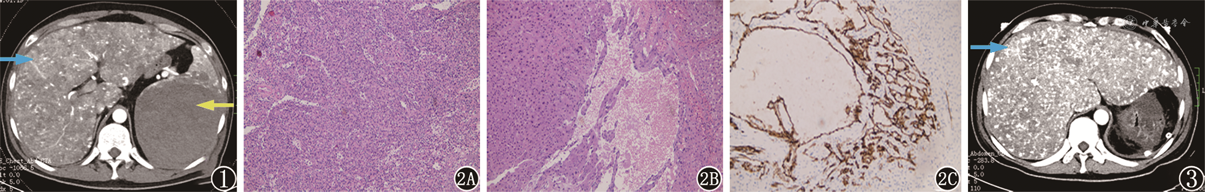

患者男,48岁,因“左上腹疼痛3周,伴小便黄染1周”入院。查体:腹膨隆,左上腹压痛、反跳痛,肝、脾区叩痛,移动性浊音阳性;家族史:叔叔因“肝病”去世。腹部CT(图1):肝内呈弥漫性雪花样改变提示肝脏、脾脏弥漫性病变,考虑遗传性出血性毛细血管扩张症(hereditary hemorrhagic telangiectasia,HHT)并动静脉瘘;脾脏较大肿块合并出血,考虑血管瘤。Hb 66 g/L,急诊全麻行脾切除、肝组织活检术,术中盆腹腔内约3 000 ml暗红色积血,肝脏呈肝硬化改变,表面可见多发小血管瘤样改变,脾脏下极见大小15 cm× 12 cm× 10 cm肿瘤,膈肌面破裂出血。术后病理:(1)脾脏血管内皮瘤(图2A);(2)肝组织镜下肝实质内灶状小血管扩张呈海绵状血管瘤样改变(图2B)。免疫组化:脾脏肿瘤:CD34、CD31、ERG均为阳性;肝组织活检:CD34(图2C)、CD31阳性、Hepatocyte阴性。术后复查肝功能损伤进行性加重。术后腹部CT(图3)示肝脏弥漫性病变增加。术后第4天患者出现肾功能不全,呼吸衰竭,肺动脉高压,心肺功能不全,脓毒血症。患者拒绝行肝移植手术,家属要求转回当地医院治疗,出院后一周随访患者已死亡。